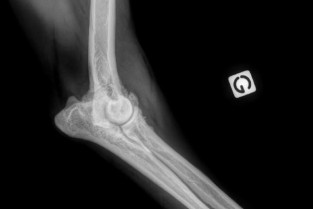

Probablement surdiagnostiquée chez le Chien, l’arthrose est encore insuffisamment suspectée chez le chat.

Chez le vieux chien qui boite, c’est souvent un diagnostic rapide associé à un traitement anti-inflammatoire et finalement, un propriétaire pas toujours satisfait du temps consacré à son animal vieillissant.

Chez le Chat, la nécessité de dissimuler la douleur fait qu’elle est trop rarement détectée et explorée.

Les dernières études montrent pourtant que cette pathologie impacte lourdement la qualité de vie de nos carnivores domestiques alors que maintenant les moyens thérapeutiques sont nombreux et efficaces.

- de connaître la physiopathologie de l’arthrose chez le Chien et le Chat ;

- d'en reconnaitre les symptômes ou savoir la suspecter ;

- d'en établir le diagnostic et de proposer un bilan complet au propriétaire ;